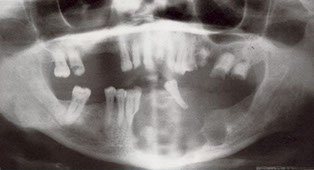

Dentigerous Cyst

- aka follicular cyst, odontogenic cyst

2nd MCC of odontogenic cyst (~1/5 epithelium-lined jaw cysts), and the MCC of developmental odontogenic cyst; usually in young adults and teens

- assoc c crown of an unerupted (or partially erupted) tooth, usually the mandibular third molars (wisdom teeth)

- may be found on radiographs taken for delayed tooth rupture; usually painless, can be painful if infected; can be large enough to displace involved teeth and cause resorption of adjacent teeth

Imaging: usually a well-defined, unilocular radiolucency on X-ray c sclerotic rim (can look the same as KCOT and ameloblastoma)

Px: excellent, almost never recur c complete enucleation